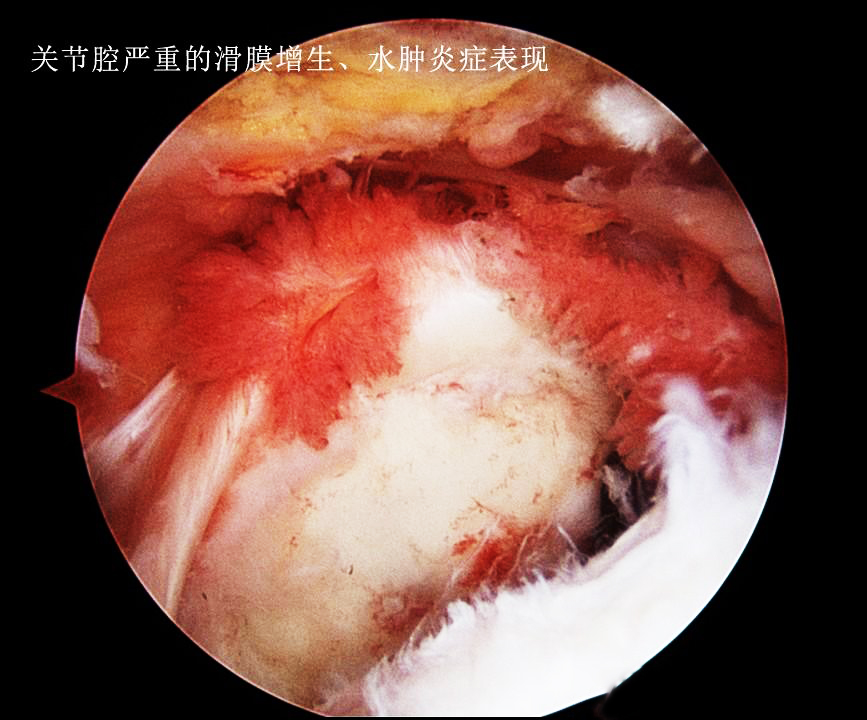

简单的说,无论是骨性关节炎还是痛风性关节炎,甚至半月板的损伤等导致关节积液的原因,主要是由于各种疾病的病理改变会刺激到关节内的一个重要结构,就是滑膜。滑膜一旦被刺激到就会产生无菌性的炎症,从而导致渗出,这就是关节积液的由来,类似于眼睛里进了沙子就会流眼泪。翻遍手机也没有找到膝关节内滑膜炎的照片,可能是被无意当中删掉了,但是大家可以用肩关节的滑膜炎的照片理解一下滑膜炎症到底是什么样子的。

大家可以看看发炎的滑膜是这个样子的,它的表面是布满了新生血管的。这张照片还不是比较重的,严重的膝关节内滑膜炎会导致整个关节腔内都布满这种肿胀增生的滑膜组织。谢医生第一次做关节镜看见这种严重增生伴有无菌性炎症滑膜的时候,印象是一种海洋的生物---海葵。

看起来这些病态的滑膜就像是魔鬼的触角一样恐怖,事实也是如此,尤其是对于类风湿关节炎以及痛风性关节炎的患者,这些滑膜会在关节内长久的存在,不断侵蚀关节的软骨以及骨骼。下图就是一例严重类风湿关节炎患者的核磁片子,他的关节软骨以及骨骼看起来已经像是被老鼠啃噬过一样了,这都归咎于类风湿滑膜炎的侵犯!